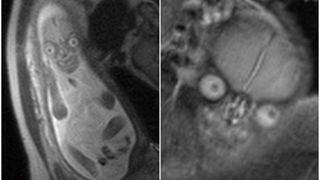

Mai multe sectii ale unui spital din Johannesburg, dar si maternitatea au fost inchise dupa ce sase nou nascuti au murit in urma infectarii cu Klebsiella pneumonia, potrivit AFP.

Din luna iulie, spitalul Thelle Mogoerane din Johannesburg se confrunta cu cazuri de infectie cu bacteria rezistenta la antibioticele uzuale, dupa cum a precizat duminica ministrul sud-african al Sanatatii, Aaron Motsoaledi. "Nu mai putem primi nou-nascuti aici", a precizat Motsoaledi pentru presa.

Bacteria, care a ucis sase nou...